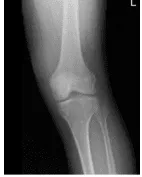

Left Knee X-ray AP and Lateral with Obliques 3 views

X-ray results were presented during the visit and showed no significant degenerative changes. There are no acute fractures. There is no fracture, subluxation, or dislocation. No osteoblastic or osteolytic lesions can be identified. The joint spaces are preserved. The subarticular cortex is smooth. A joint effusion is demonstrated.